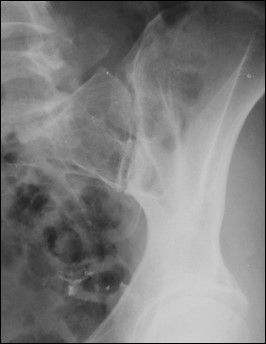

What is the CR angle for an AP axial SI joint projection (male)?

30° cephalad.

What is the CR angle for an AP axial SI joint projection (female)?

35° cephalad.

Where is the CR centered for an AP axial SI joint projection?

5–6 cm below the ASIS.

<p>5–6 cm below the ASIS.</p>

What is the CR angle for a PA axial SI joint projection?

35° caudad.

Where does the CR exit for a PA axial SI joint projection?

ASIS.

Which SI joint is shown in an AP oblique projection?

The joint of the raised side.

<p>The joint of the raised side.</p>

What is the degree of obliquity for oblique SI joint projections?

25–30° patient obliqued.

Where is the CR for oblique SI joint projections?

1" medial to the raised ASIS.

<p>1" medial to the raised ASIS.</p>

What does excess obliquity do in an oblique SI joint projection?

Closes the inferior joint space.

<p>Closes the inferior joint space.</p>

What does insufficient obliquity do in an oblique SI joint projection?

Closes the superior joint space.

<p>Closes the superior joint space.</p>

What structures are shown in an oblique SI joint projection?

SI joint, sacral ala, ilium.

<p>SI joint, sacral ala, ilium.</p>

What does an elongated sacrum indicate in an axial SI joint projection?

Correct CR angle.

What indicates no rotation in an AP axial SI joint projection?

Symmetric SI joints.

<p>Symmetric SI joints.</p>